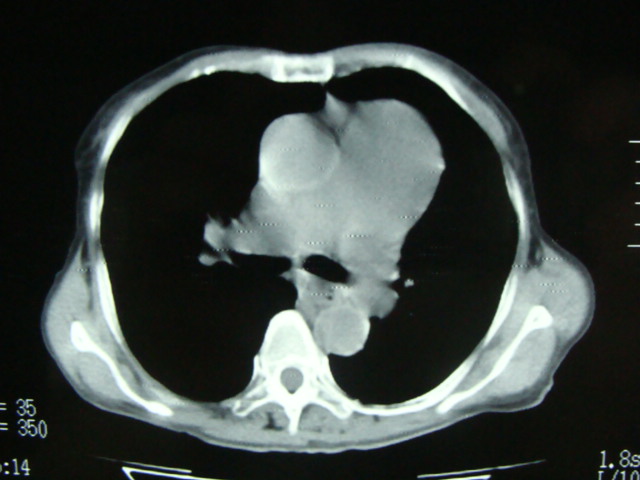

标题: CT13799:风心?肺动脉发育异常?

xxx女.72岁,胸闷不适,一侧下肢水肿.肺窗没见异常.不上传.

肺动脉根部,右室增宽;肺门小;是什麽征象///

右肺动肺截断.肺动肺脉高压

主肺动脉扩张,腹水.

考虑:1、肺动脉高压(原因?);